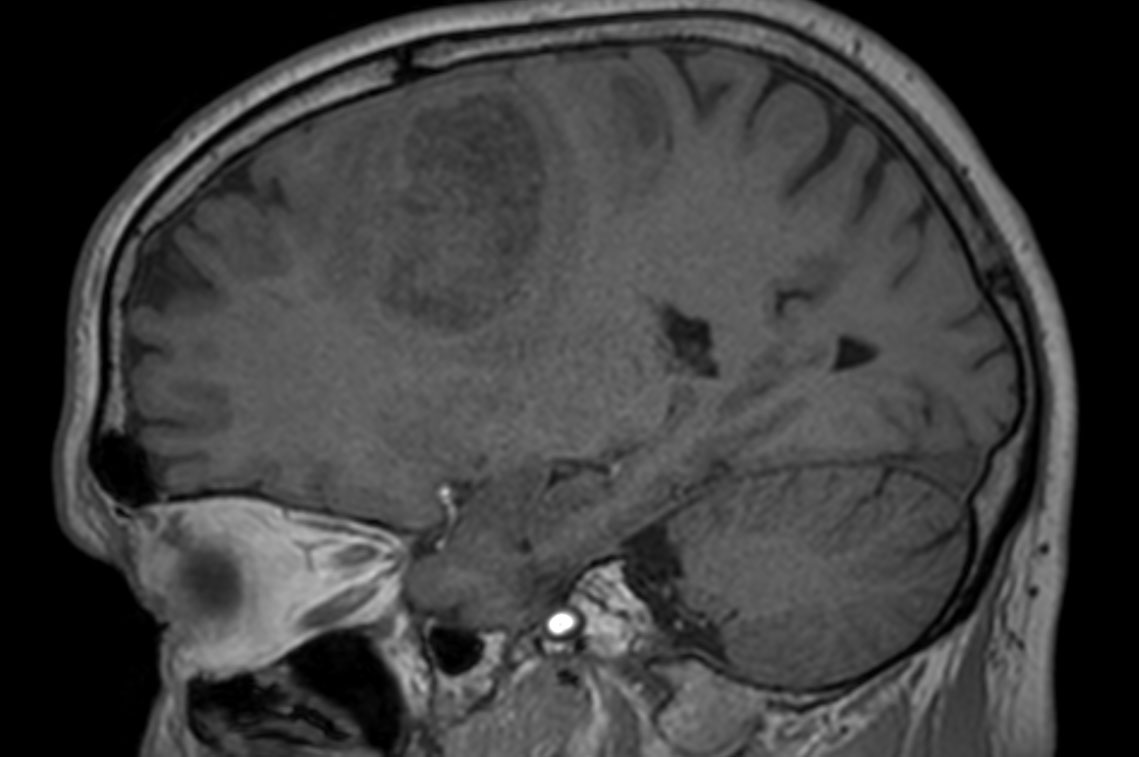

Patient with a revasculerized area with small bleedings. Diagnosed as malignant glioblastoom.

3D T1w TFE (sagittal reformat)